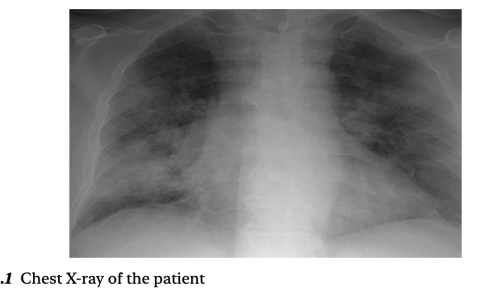

A 34-year-old woman with human immunodeficiency virus (HIV) infection presented with a 3-day history of a blind spot in her right eye. One week before the current presentation, the HIV viral load was 57 copies per milliliter (reference value, <20) and the CD4 cell count was 81 per cubic millimeter (reference range, 500 to 1500). On eye examination, visual acuity was 20/50 in the right eye and 20/20 in the left eye. Fundoscopy of the right eye revealed fulminant retinitis with dense areas of retinal necrosis and hemorrhage. The left eye, which had been asymptomatic, had similar changes. What is the diagnosis?